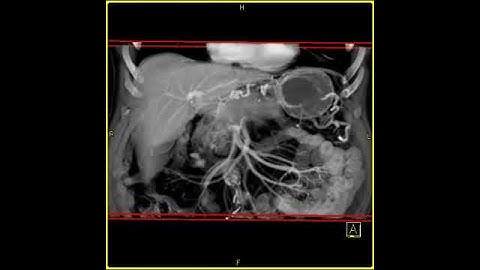

AUTOMATIC SEGMENTATION OF PANCREAS AND PANCREATIC TUMOR USING DEEP LEARNING